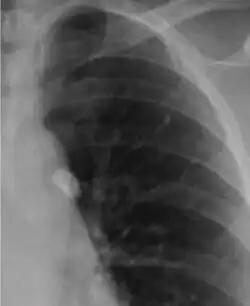

Chest X-ray of a Ghon's focus

A Ghon focus is a primary lesion usually subpleural, often in the mid to lower zones, caused by Mycobacterium bacilli (tuberculosis) developed in the lung of a nonimmune host (usually a child).[1] It is named for Anton Ghon (1866–1936), an Austrian pathologist.

It is a small area of granulomatous inflammation, only detectable by chest X-ray if it calcifies or grows substantially (see tuberculosis radiology).[2] Typically these will heal, but in some cases, especially in immunosuppressed patients, it will progress to miliary tuberculosis (so named due to the granulomas resembling millet seeds on a chest X-ray).[2]